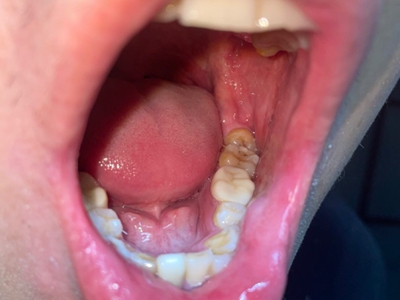

阻生牙是指由于邻牙、骨或软组织的阻碍而只能部分萌出或完全不能萌出,且以后也不能萌出的牙。引起牙阻生的成因,主要是由于颌骨缺乏足够的空间容纳全部恒牙。常见的阻生牙为下颌第三磨牙、上颌第三磨牙及上颌尖牙。

阻生牙可反复引起冠周炎,或引起邻牙牙根吸收和破坏,位置不正,不能完全萌出,好发部位是上、下颌第三磨牙。